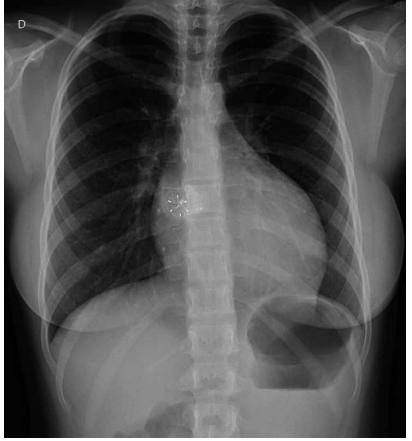

Paciente de 1 ano e 11 meses deu entrada no Pronto-

-Socorro com história de ânsia de vômito, palidez, sudorese e cianose ontem, sem perda de consciência. Hoje,

refere novo quadro de cianose e palidez com saturação

de 65% em ar ambiente, segundo aferição com o aparelho da mãe. Na avaliação atual, a saturação periférica da

criança em ar ambiente foi de 95%. Mãe refere que, com

3 dias de vida, teve diagnóstico de cardiopatia congênita

e bloqueio atrioventricular total, necessitando de implante de marca-passo definitivo, além de quadro convulsivo

(segue com neurologista), mas nunca havia ficado roxa

antes. Qual é a cardiopatia congênita provável associada

ao bloqueio atrioventricular? Considere a radiografia de

tórax atual a seguir.